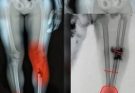

Kaleb was born with Osteogenesis Imperfecta, a condition that causes bones to break very easily. Because of this disorder, even small movements or minor accidents can result in fractures. Throughout his young life, Kaleb experienced more than 200 bone fractures, a number that reflects just how difficult his journey truly was.

Despite the physical pain and constant medical challenges he faced, Kaleb’s spirit remained remarkably positive. Much of his childhood involved hospital visits, surgeries, treatments, and long periods of physical therapy. Yet people who met him often spoke about his courage and the way he carried himself with confidence and kindness.